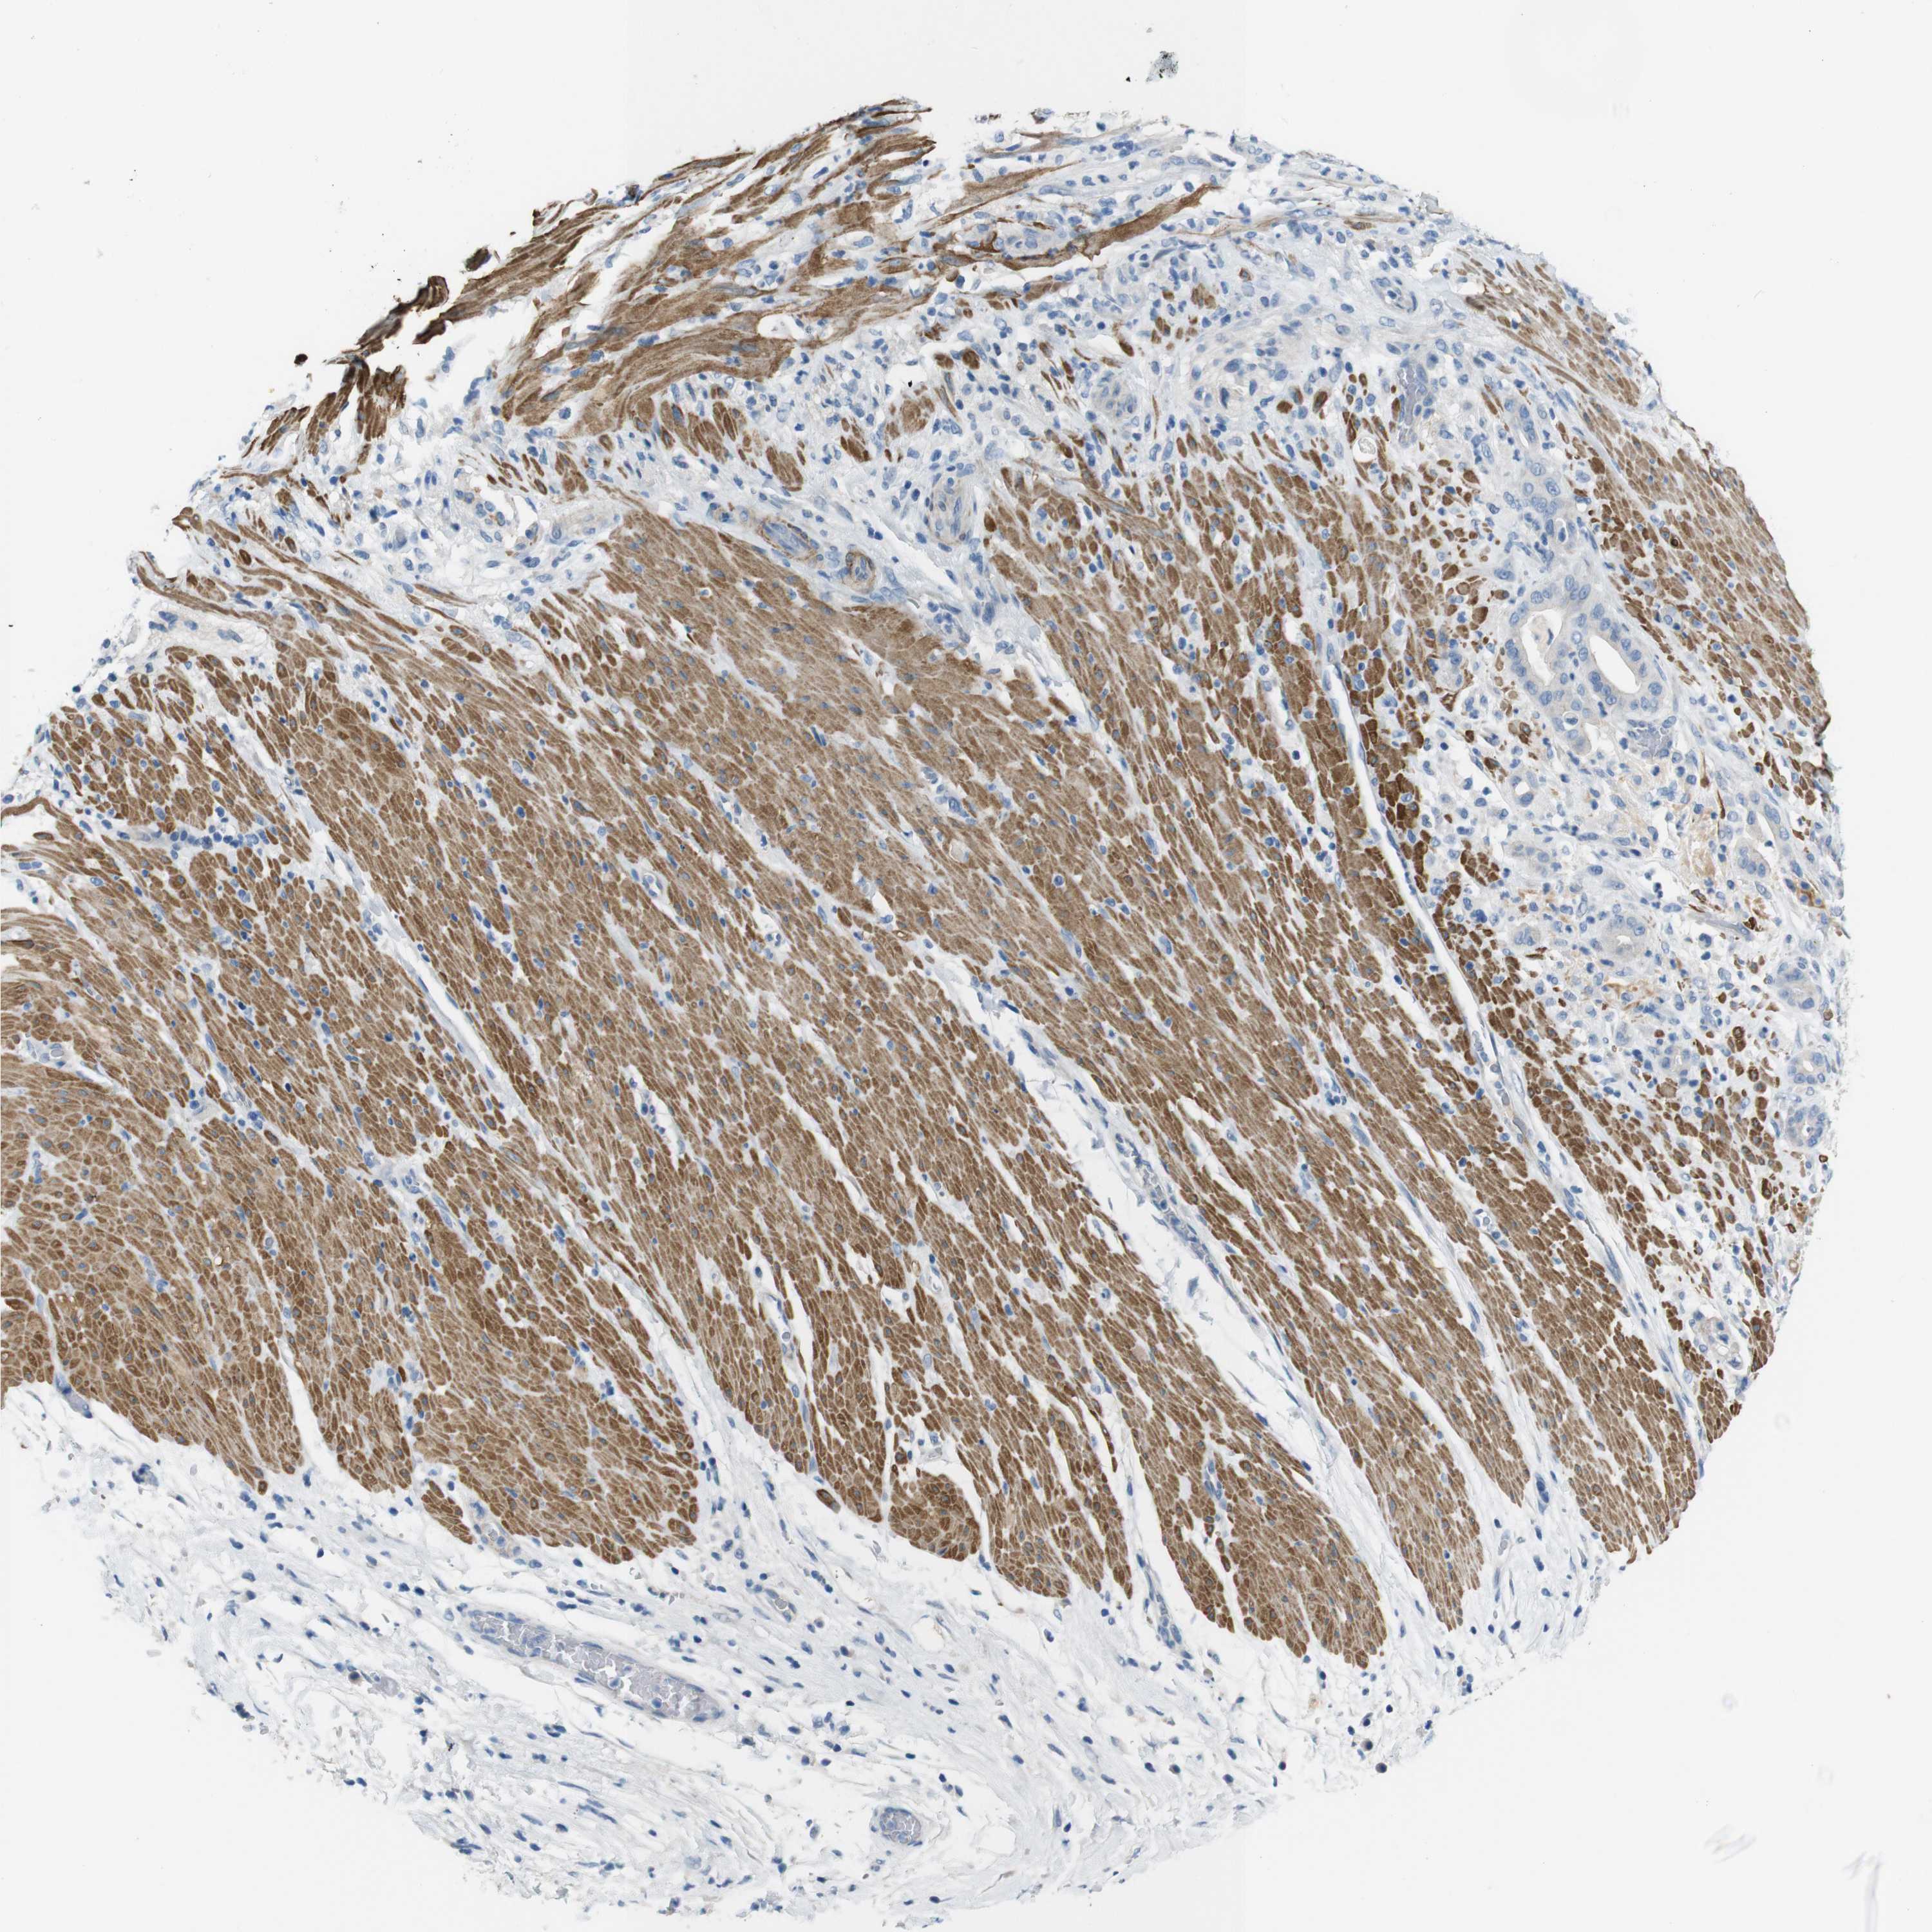

PANCREATIC CANCER - Protein expressioni

A mouse-over function shows sample information and annotation data. Click on an image to view it in a full screen mode. Samples can be filtered based on level of antibody staining by selecting one or several of the following categories: high, medium, low and not detected. The assay and annotation is described here.

Note that samples used for immunohistochemistry by the Human Protein Atlas do not correspond to samples in the TCGA dataset.

Antibody stainingi

Antibody staining in the annotated cell types in the current human tissue is reported as not detected, low, medium, or high, based on conventional immunohistochemistry profiling in selected tissues. This score is based on the combination of the staining intensity and fraction of stained cells.

Each image is clickable and will lead to virtual microscopy that enables deeper exploration of all samples and also displays staining intensity scores, fraction scores and subcellular localization as well as patient and tissue information for each sample.

Antibody HPA013770

Staining

High

Medium

Low

Not detected

Intensity

Strong

Moderate

Weak

Negative

Quantity

>75%

75%-25%

<25%

None

Location

Nuclear

Cytoplasmic/membranous

Cytoplasmic/membranous,nuclear

Adenocarcinoma, NOS

Adenocarcinoma, metastatic, NOS